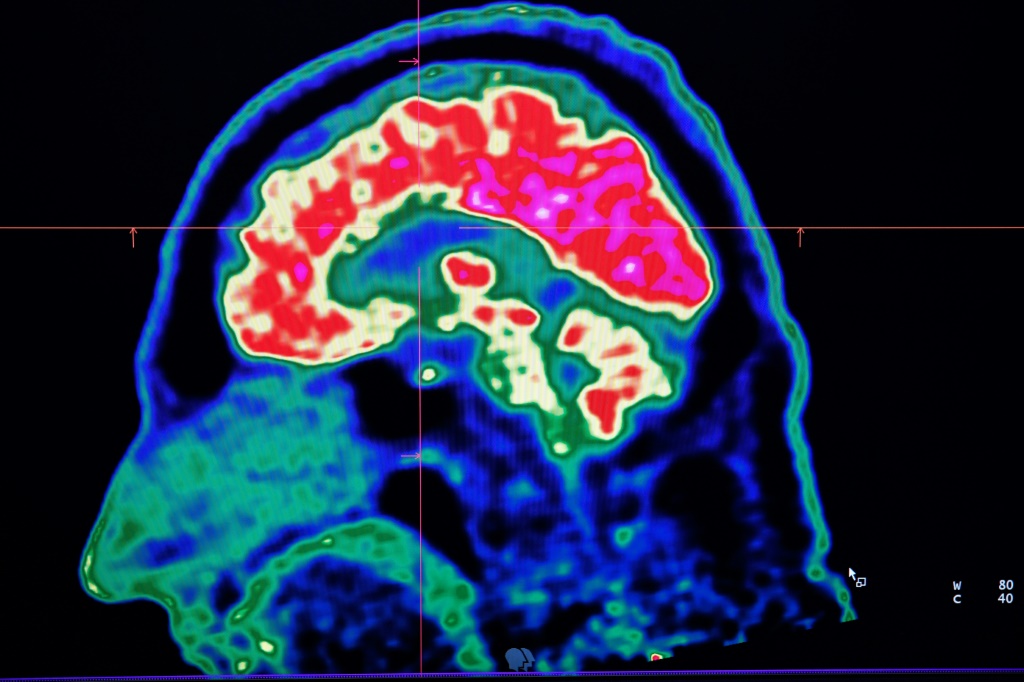

وأثناء التجربة، أمضى ثلاثة أشخاص 16 ساعة في جهاز تصوير طبي وظيفي (fMRI). وتتيح هذه التقنية تسجيل الاختلافات في تدفق الدم في الدماغ، وبالتالي الإبلاغ في الوقت الفعلي عن نشاط المناطق الدماغية أثناء مهمات معينة (الكلام والحركة وما إلى ذلك).